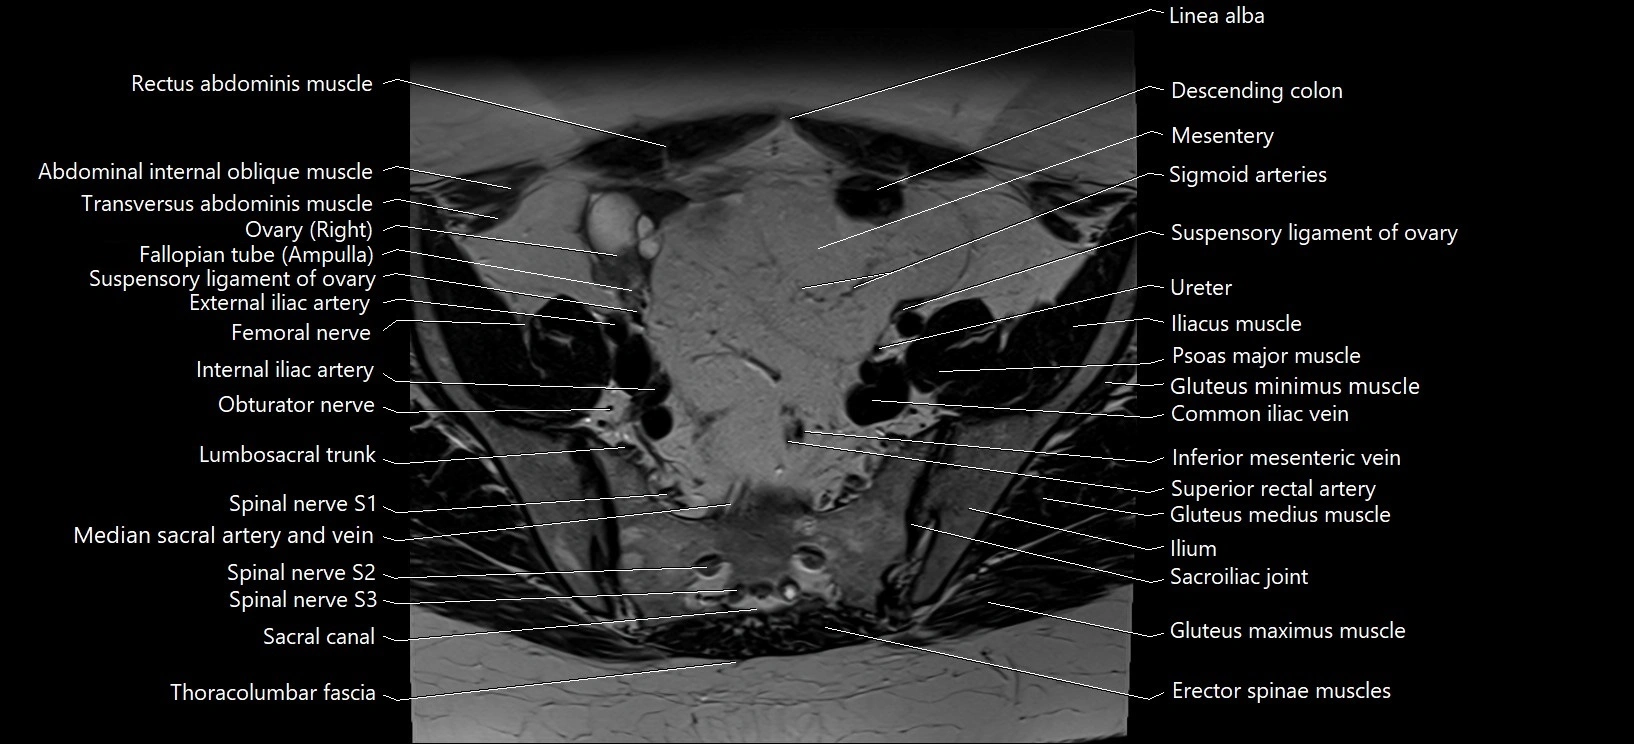

- Common iliac vein

- Erector spinae muscles

- External iliac artery

- External iliac vein

- Fallopian tube

- Femoral nerve

- Fundus of uterus

- Gluteus medius muscle

- Gluteus minimus muscle

- Iliopsoas muscle

- Inferior mesenteric artery (IMA)

- Inferior mesenteric vein

- Left ovary

- Lumbosacral trunk

- Ovaries

- Psoas major muscle

- Right ovary

- Sacral canal

- Sacroiliac joint

- Sacrum

- Sigmoid colon

- Spinal nerve S1

- Spinal nerve S2

- Spinal nerve S3

- Superior rectal artery

- Suspensory ligament of ovary

- Ureters